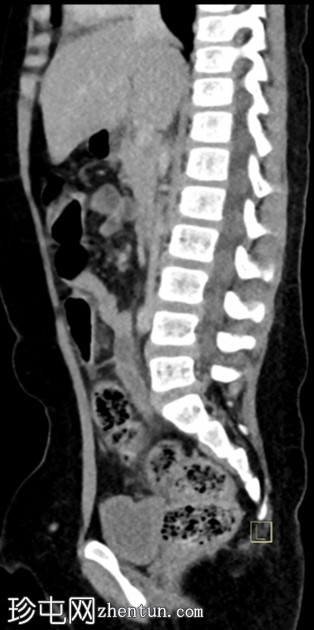

矢状位增强扫描(门静脉期)

阑尾充血膨胀,直径10 mm,轻度壁增厚及强化,周围脂肪间隙模糊。

回盲部及阑尾开口轻度壁增厚,可能为炎症性增生(回结肠炎)。

该病例的影像学表现符合急性阑尾炎的典型特征,表现为阑尾充血膨胀(最大直径10 mm),轻度壁增厚及强化,周围脂肪间隙模糊。

本病例的其他发现包括右髂窝肠系膜淋巴结肿大(反应性增生)和回盲部肠壁增厚,这可能代表反应性肠壁增厚(继发于阑尾炎),但更可能在本病例中,是炎症/感染(回结肠炎)的早期阶段,最终扩散至阑尾开口,导致阑尾开口管腔狭窄,进而发展为急性真性阑尾炎——本病例中未见阑尾粪石阻塞阑尾开口。